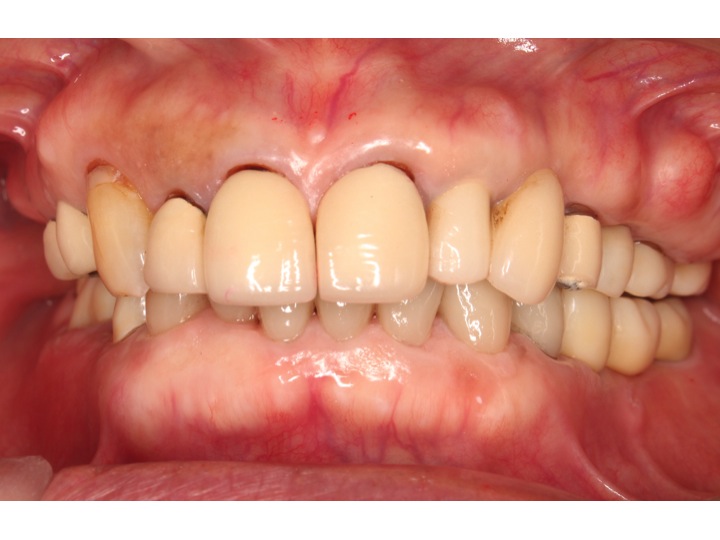

インプラントオンライン見積もりは こちらをクリック

欠損部からインプラントの治療費や治療期間(治療回数)等をお答えします。